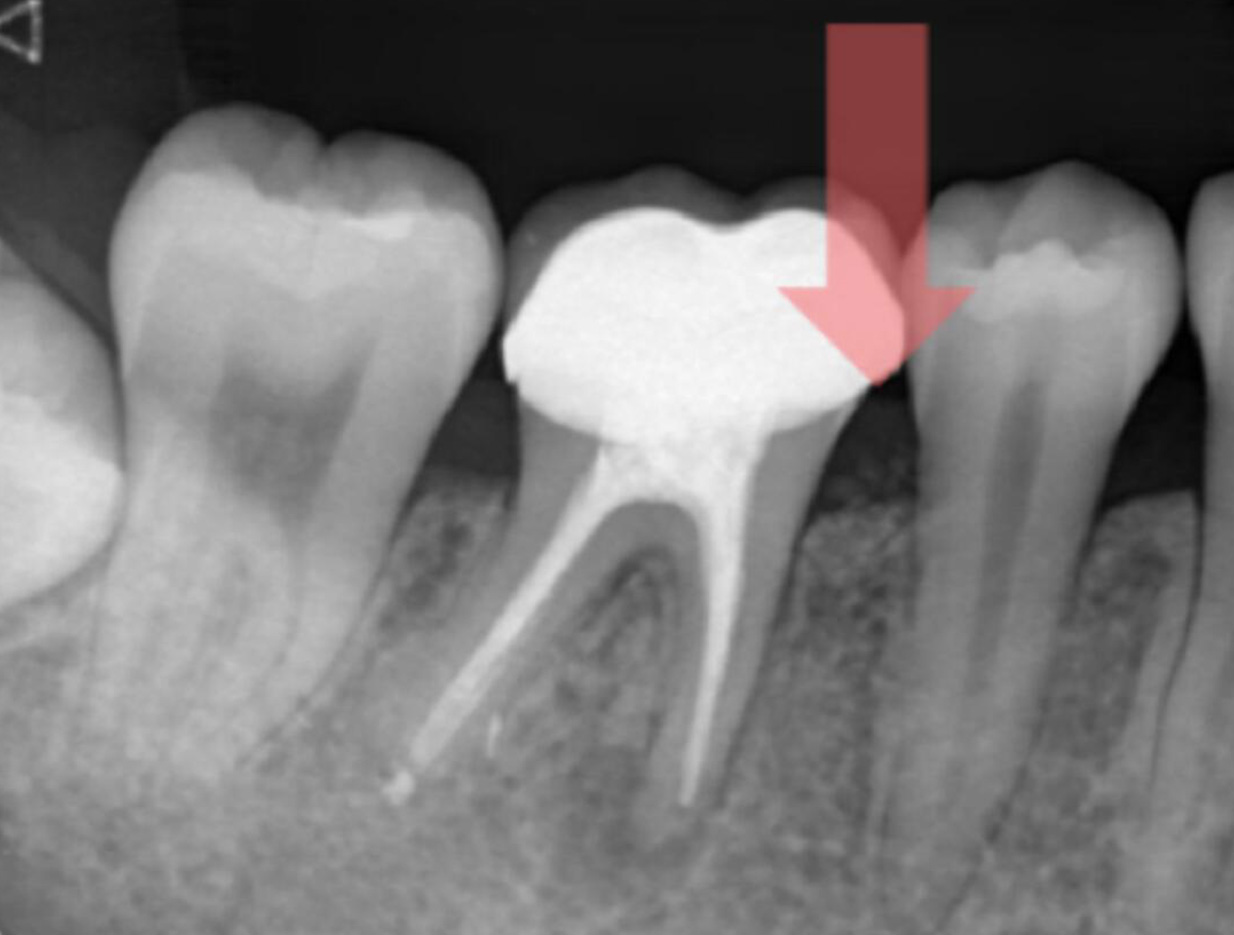

牙周再生手術後

兩年X光片(牙周骨長回)